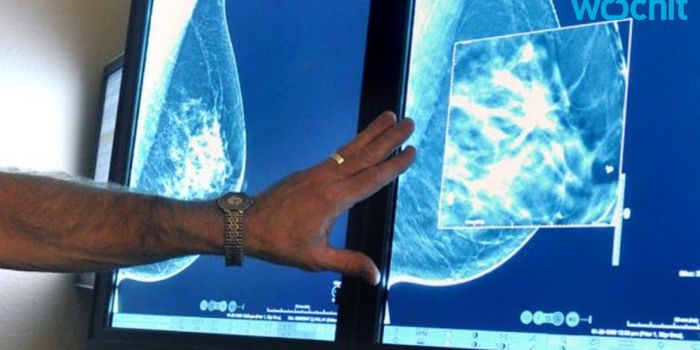

JAN 04, 2018VideosWith breast cancer, early detection is crucial. Mammograms can find small lumps and tumors, but a new blood biomarker te ...

NOV 14, 2017VideosScreenings for certain types of cancer are essential to maintaining good health. Breast cancer, cervical cancer, and col ...

OCT 18, 2017VideosIn 2016, an estimated 246,660 women in the US was diagnosed with breast cancer - a disease that currently ranks as one o ...

OCT 06, 2017VideosOctober is Breast Cancer Awareness Month; however, a recent study shows that many women are not aware of the issue of ov ...

SEP 01, 2017VideosThe effects of breast cancer can be devastating for women. Reconstruction is often performed after mastectomies, but get ...

AUG 10, 2017VideosOn the whole, rates of breast cancer cases are decreasing. However, for certain ethnic groups, the rates have been on a ...